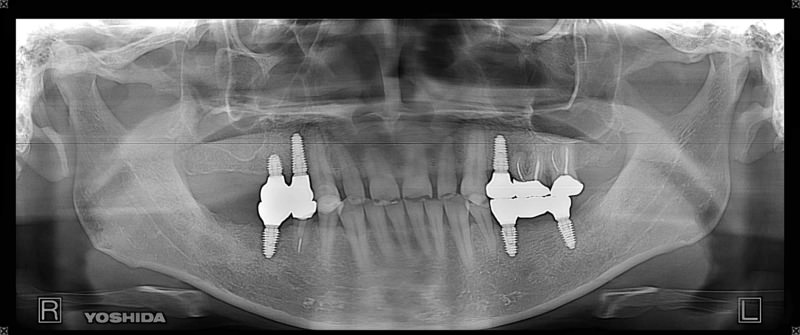

症例140代 男性 主訴 奥歯に歯を入れたい、しっかり噛みたい

治療前

治療後(5年経過)

主訴 奥歯がない為、食事が不自由である。入れ歯は煩わしいので、固定制のインプラントにして欲しいと訴え来院。口腔内全体で6本のインプラントを埋入。仮歯にて神経筋機構、顎関節のバランスを整え、リハビリを経て、約5ヶ月後にジルコニアを装着。

リスクとしては、外科的侵襲がある。デメリットは、保険外診療の為、経済的負担がある。

費用 316万(税込) (オペ・仮歯・最終補綴物まで含む)